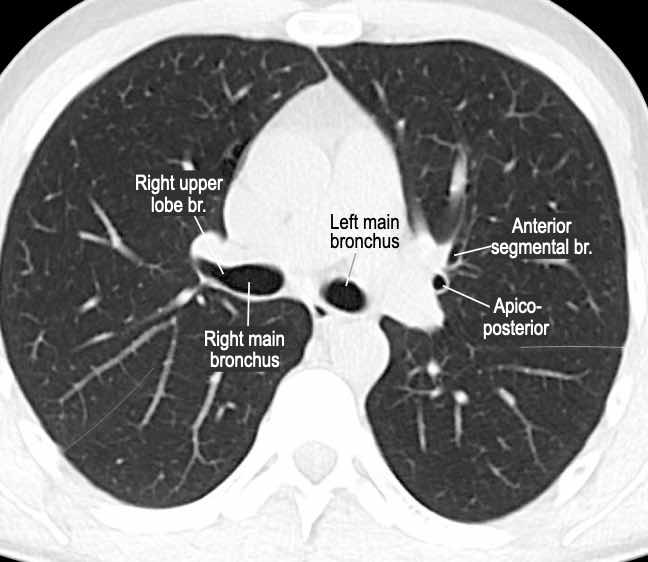

Phế quản trên CT

Cuộn qua các hình ảnh để quan sát khí quản phân chia thành phế quản chính phải và trái, sau đó tiếp tục phân chia thành các phế quản thùy và phế quản phân thùy.